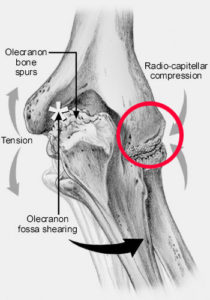

Osteochondritis Dissecans of the elbow, more commonly known as Capitellar OCD, involves a loss of blood supply to part of the cartilage within the elbow joint. When this cartilage ceases to perform its shock absorption duties, the elbow joint can become stiff, inflamed, and generally painful.

Your Capitellum is: A smooth, round, knob on the end of the humerus joined with the radius bone to form a hinge, with a shape similar to a knob and a cup.

- The capitellum endures tremendous force with activities, like throwing a baseball or gymnastics.

- The repetitive force impacts a location of bone that has relatively weak blood supply. This causes the bone to weaken, crack, and without proper blood flow, not heal.

- If a crack develops in the weakened capitellar bone, it may begin to separate, and chip away.

Red circle indicates that capitellum making contact with the radius bone. This figure also orients the next few scope images. The red circle is what the camera is visualizing.